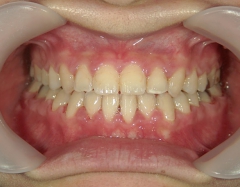

矯正歯科 治療後矯正歯科 全顎ワイヤー矯正 治療後矯正歯科(全顎ワイヤー矯正)治療後

矯正歯科 治療後

no.31_7964_治療後_右 .JPGno.31_7964_治療後_正面 .JPGno.31_7964_治療後_左.JPG